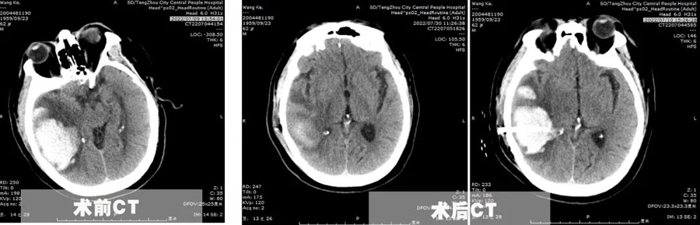

患者王先生,62歲,體重200余斤,糖尿病、冠心病、腦梗塞病史3年余,長期口服二甲雙胍、阿司匹林、瑞舒伐他汀等藥物,病情控制一般。7月8日,患者突發頭痛頭暈,出現一側肢體偏癱、意識障礙,急診行顱腦CT提示枕頂葉大面積腦出血,血腫量超過50ml,有手術指征。

為了在最恰當的手術時機及時完成手術,7月10日,李永濤主任放棄在家休息的時間,帶領陳凡宇主治醫師,在局麻下為患者完成顱骨鉆孔腦出血引流術。術中僅在切口線注入5ml利多卡因,然后顱骨鉆孔形成直徑約1cm骨孔,切開硬腦膜后精準置入直徑約5mm的硅膠引流管于血腫腔,術后復查CT并引流管內注入尿激酶促進血腫引流。經過3天的引流,血腫基本排除,腦壓下降,癥狀改善。同時盡早給予患者床旁肢體功能康復,并積極調整患者血糖、血壓、及心臟功能,給予患者精神鼓勵和心理輔導。患者出院的時候已經能夠獨立行走,生活自理。